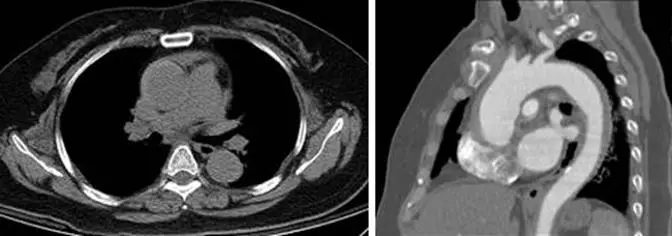

50歲男性至急診就醫,主訴突發性胸痛持續逾半小時,胸部電腦斷層影像如附圖,正確診斷為:

從提供的CT影像可觀察到:

- 橫斷面(左圖)於升主動脈壁旁見到一側性(Crescent-shaped)高密度帶狀增厚,與主動脈腔無明顯連通,也未見典型的瓣膜撕裂(intimal flap)或真假腔分離;此區高密度與未增強條件下的主動脈腔比對,呈現相對增高之血腫密度。

- 矢狀重組(右圖)顯示自主動脈根部起即向上、向後壁厚呈均勻增厚,並未見血管內膜撕裂延伸的間隔或假腔造影劑充填;壁外形成之高密度帶緊貼升主動脈,證實病灶累及升主動脈。

上述影像符合典型IMH表現:非增強CT見高密度血腫,對比增強CT僅見平滑壁增厚但無偽腔或撕裂口,且主要分佈於升主動脈處 (pmc.ncbi.nlm.nih.gov)。